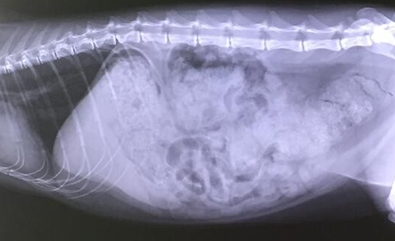

- Darmverschluss, Darminvagition, Gallenstau mit und ohne Gelbsucht, Tumoren und Polypen

- bildgebenden Verfahren